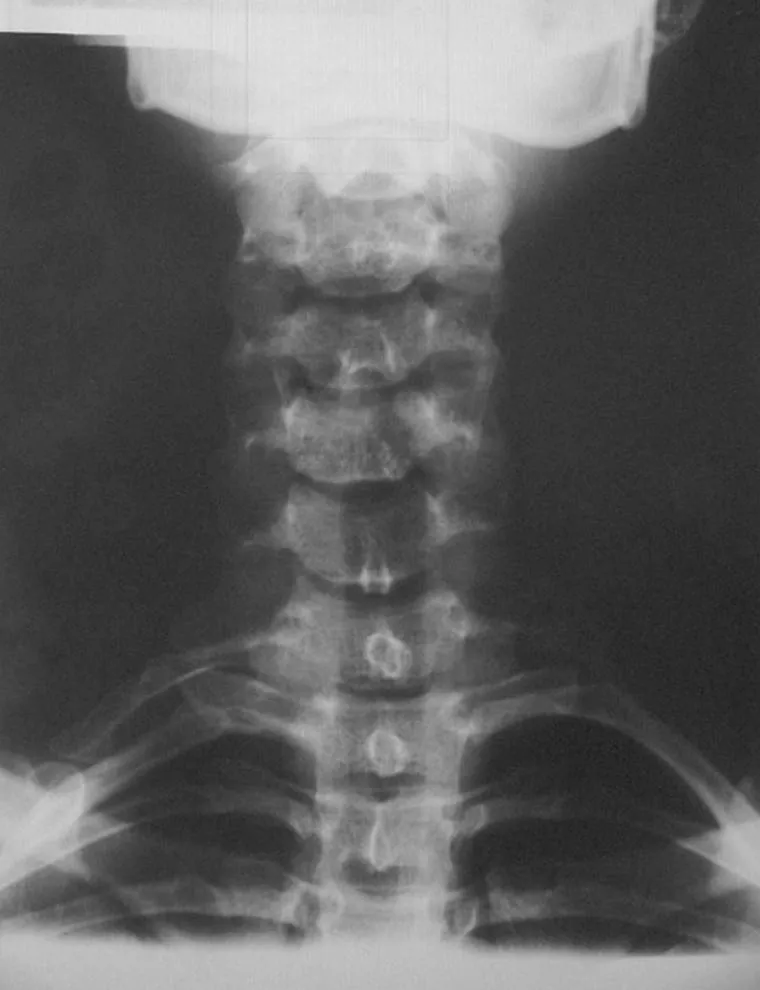

Nyaki borda röntgenfelvételen

Nyaki bordák a hetes, egyoldali a hatos nyakcsigolyán

A csontos mellkas és a gerinc veleszületett fejlődési rendellenességei közül a nyaki borda, a hetes nyakcsigolya hosszabb harántnyúlványa és a scoliosis (gerincferdülés) okozza a legtöbb panaszt.

A nyaki borda és a hetes nyakcsigolya oldalsó nyúlványának sebészi eltávolítását egyértelműen bizonyító radiológiai lelet birtokában, a fennálló keringési és idegrendszeri elváltozások alapján indokolt elvégezni, mérlegelve a műtéti sebzés gyógyulása során keletkező hegszövet esetleges térszűkítő hatását.